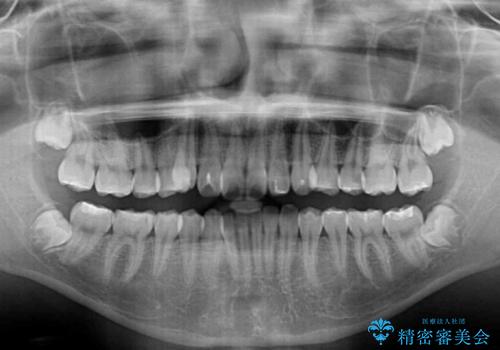

- 八重歯を気にして来院された高校生の患者様です。

八重歯を効率よく改善するため、補助装置を使用して上顎の奥歯を後方に移動させました。